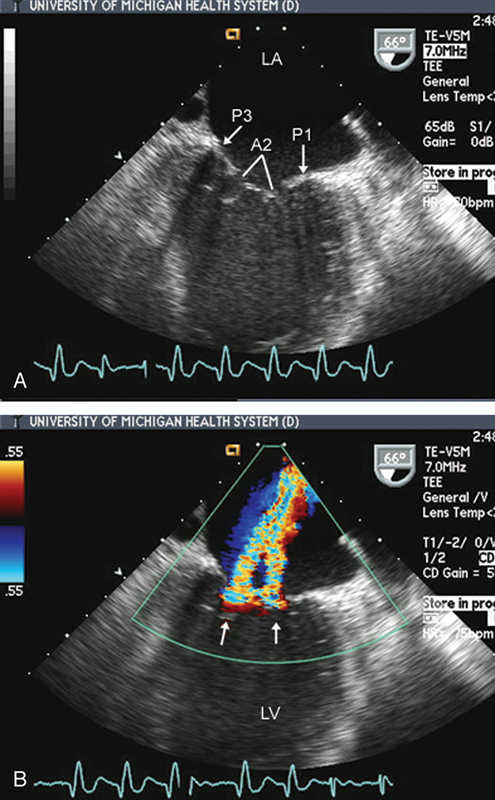

فحوصات تشخيصية لبعض امراض القلب والشرايين التاجية